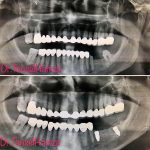

Diş Estetiği ve İmplant (Bölüm 3)

Tansel Hamza